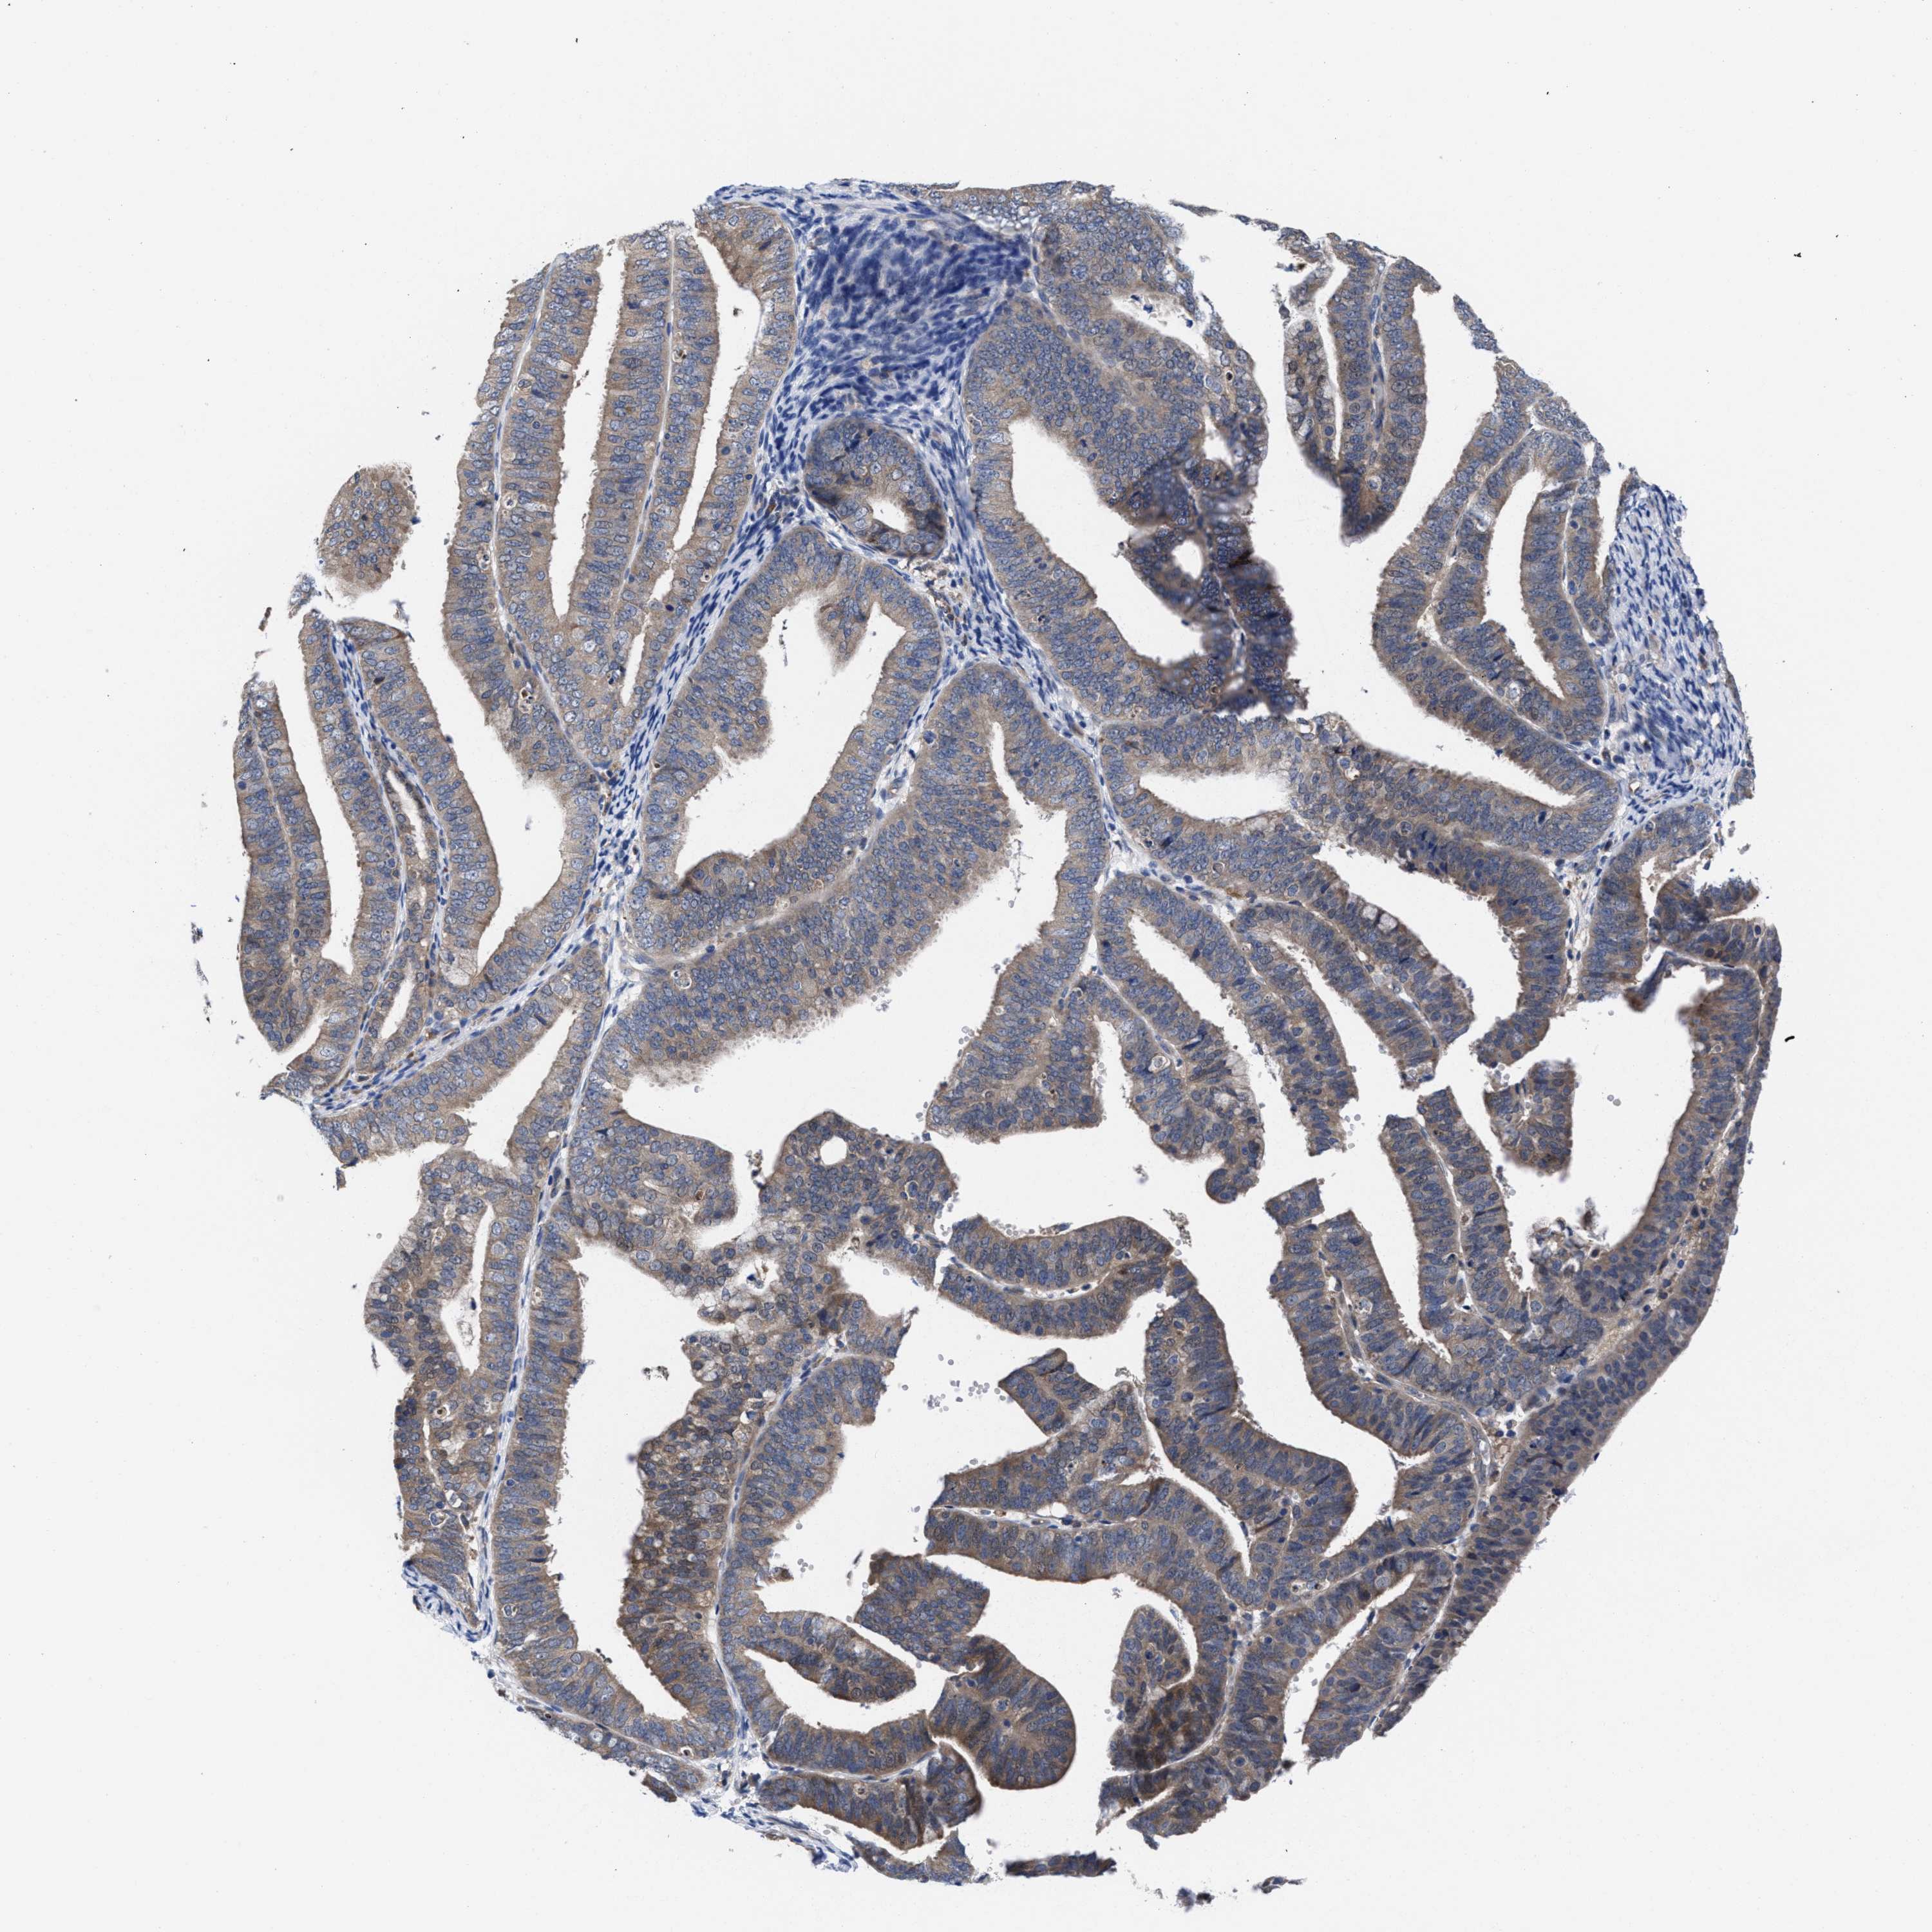

ENDOMETRIAL CANCER - Protein expressioni

A mouse-over function shows sample information and annotation data. Click on an image to view it in a full screen mode. Samples can be filtered based on level of antibody staining by selecting one or several of the following categories: high, medium, low and not detected. The assay and annotation is described here.

Note that samples used for immunohistochemistry by the Human Protein Atlas do not correspond to samples in the TCGA dataset.

Antibody stainingi

Antibody staining in the annotated cell types in the current human tissue is reported as not detected, low, medium, or high, based on conventional immunohistochemistry profiling in selected tissues. This score is based on the combination of the staining intensity and fraction of stained cells.

Each image is clickable and will lead to virtual microscopy that enables deeper exploration of all samples and also displays staining intensity scores, fraction scores and subcellular localization as well as patient and tissue information for each sample.

Antibody HPA022931

Staining

High

Medium

Low

Not detected

Intensity

Strong

Moderate

Weak

Negative

Quantity

>75%

75%-25%

<25%

None

Location

Nuclear

Cytoplasmic/membranous

Cytoplasmic/membranous,nuclear

Adenocarcinoma, NOS

Adenoma, NOS